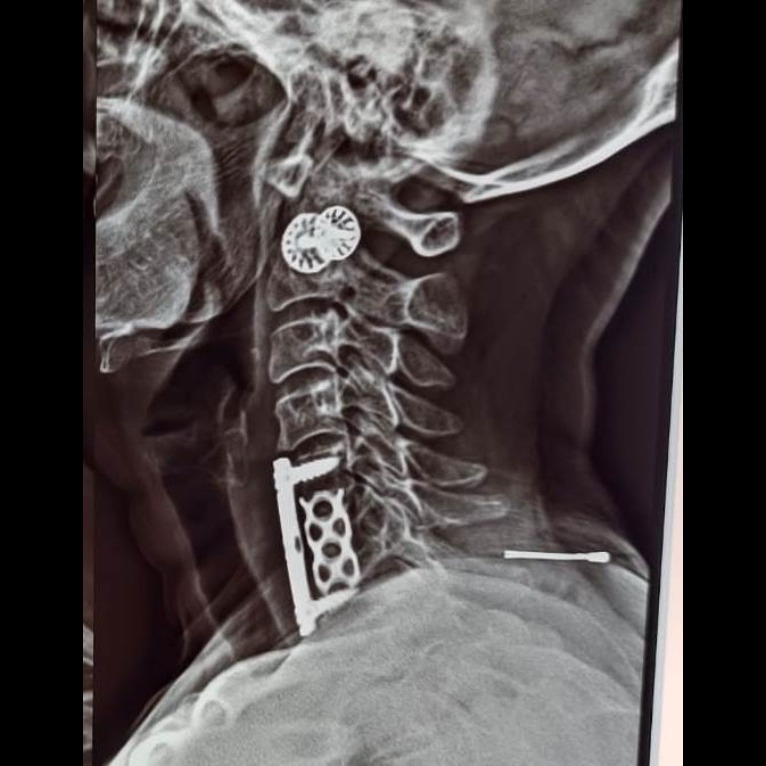

CASE OF CERVICAL SPINE INFECTION WITH VERTEBRAL BODY DAMAGE WITH ABSCESS FORMATION WITH SPINAL CORD COMPRESSION C5-C6, C6-C7 BED RIDDEN PATIENT QUADRIPERESIS (POWER REDUCED IN BOTH UPPER LIMBS AND BOTH LOWER LIMBS) SURGERY :- ANTERIOR CERVICAL SPINE FIXATION WITH DECOMPRESSION DISCECTOMY WITH INTERBODY CAGE WITH PLATTING. PROCEDURE :- DAMAGED C-6 VERTEBRAL BODY REMOVED C5-6 AND C6-7 DISC, INFECTED AND NECROTIC TISSUE REMOVED ABSCESS DRAINAGE DONE SPINAL CORD DECOMPRESSION DONE INTERBODY MASH CAGE INSERTED PLATE FIXED WITH SCREWS INFECTED TISSUE SEND FOR BIOPSY AND LAB EXAMINATIONS ANTIBIOTICS GIVEN FOR LONG TIME ADVANTAGE :- *DONE THROUGH VERY SMALL HOLE BY USING ADVANCED MICROSCOPE – MAGNIFIED IMAGE OF NERVES, MUSCLES AND BLOOD VESSELS – SO NO CHANCE OF DAMAGE TO CRITICAL ORGANS *NO MUSCLE DAMAGE - ONLY MUSCLE RETRACTED *VERY LESS BLOOD LOSS *SMALL INCISION – COSMETIC GOOD *FAST RECOVERY *EARLY DISCHARGE FROM HOSPITAL